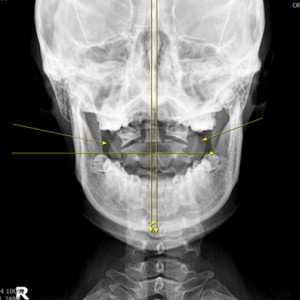

안면 균형검사

턱의 다양한 각도 사진 촬영

Catch Point 02. 눈썹 높이!

눈높이를 바로 잡아라!

22개 머리뼈를 바르게

굳은 근육을 부드럽게

눈썹 높이 바르게

어지럼증, 두통 개선